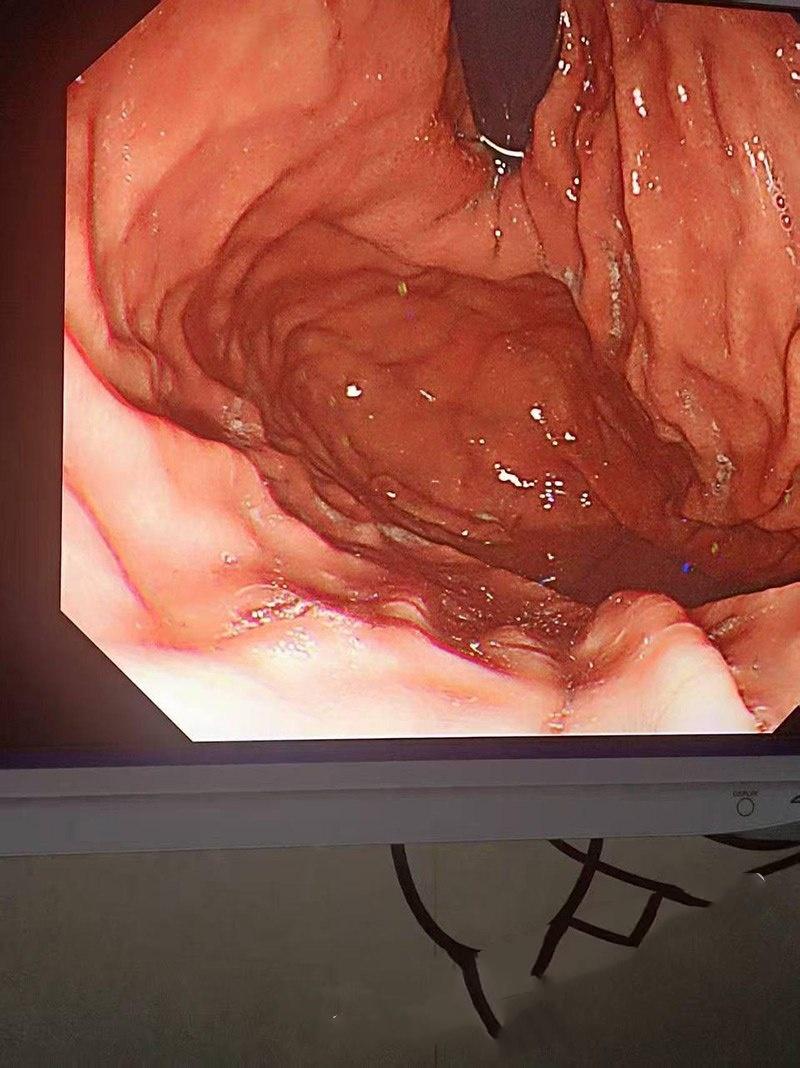

当大佬从男模屁眼将手抽出来时,金戒指竟然卡落在男模屁眼里拿不出来了,没办法,只好深夜送医,在医生专业操作下拿出那枚戒指,不得不说现在的有钱人玩的真花,大家还记得高尔夫球事件吗?这次事件更是有过之而不及。